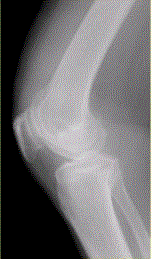

问题 患者女,54岁,右膝关节痛。实验室检查:类风湿因子阳性,除外膝关节类风湿性关节炎。X线检查结果如下图。 判断类风湿性关节炎活动性的检查方法是

选项 A.CR B.CT C.MRI D.MRI增强检查 E.动态增强MRI

答案 E